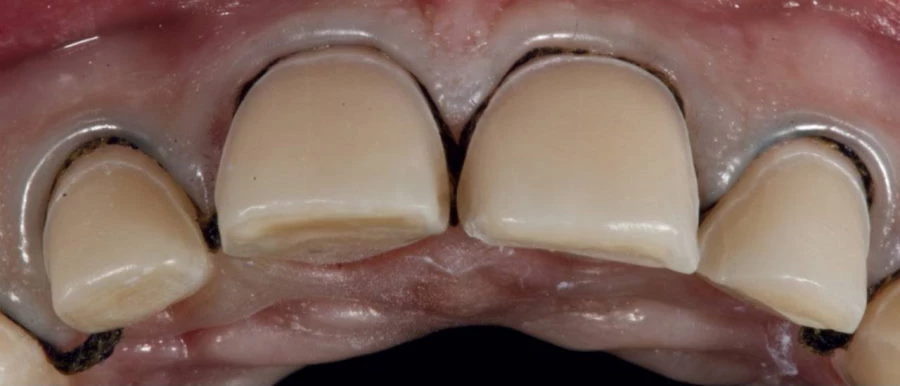

Nagy előnyük, hogy elkészítésük után nem jelentkezik szürkés vonal az íny szélén, mint bizonyos esetekben a fémkerámia fogkorona használatakor. Ennek oka az, hogy a kerámia foghéj fémmentes anyagból készül.

A héjkerámia a fog saját szöveteihez hasonlóan a fény számára átjárható, transzparens. Ezzel a tulajdonságával rendkívül magas esztétikai eredmény érhető el, így szinte lehetetlen megmondani, hogy a páciens saját fogait látjuk, vagy a héjkerámia fogpótlásokat.

Az esztétikia fogászati beavatkozások során, rendelőnkben a héjakat IPS e.max® préskerámiából készítjük, amivel kellően ellenálló, pontos és gyönyörű végeredményt érhetünk el.